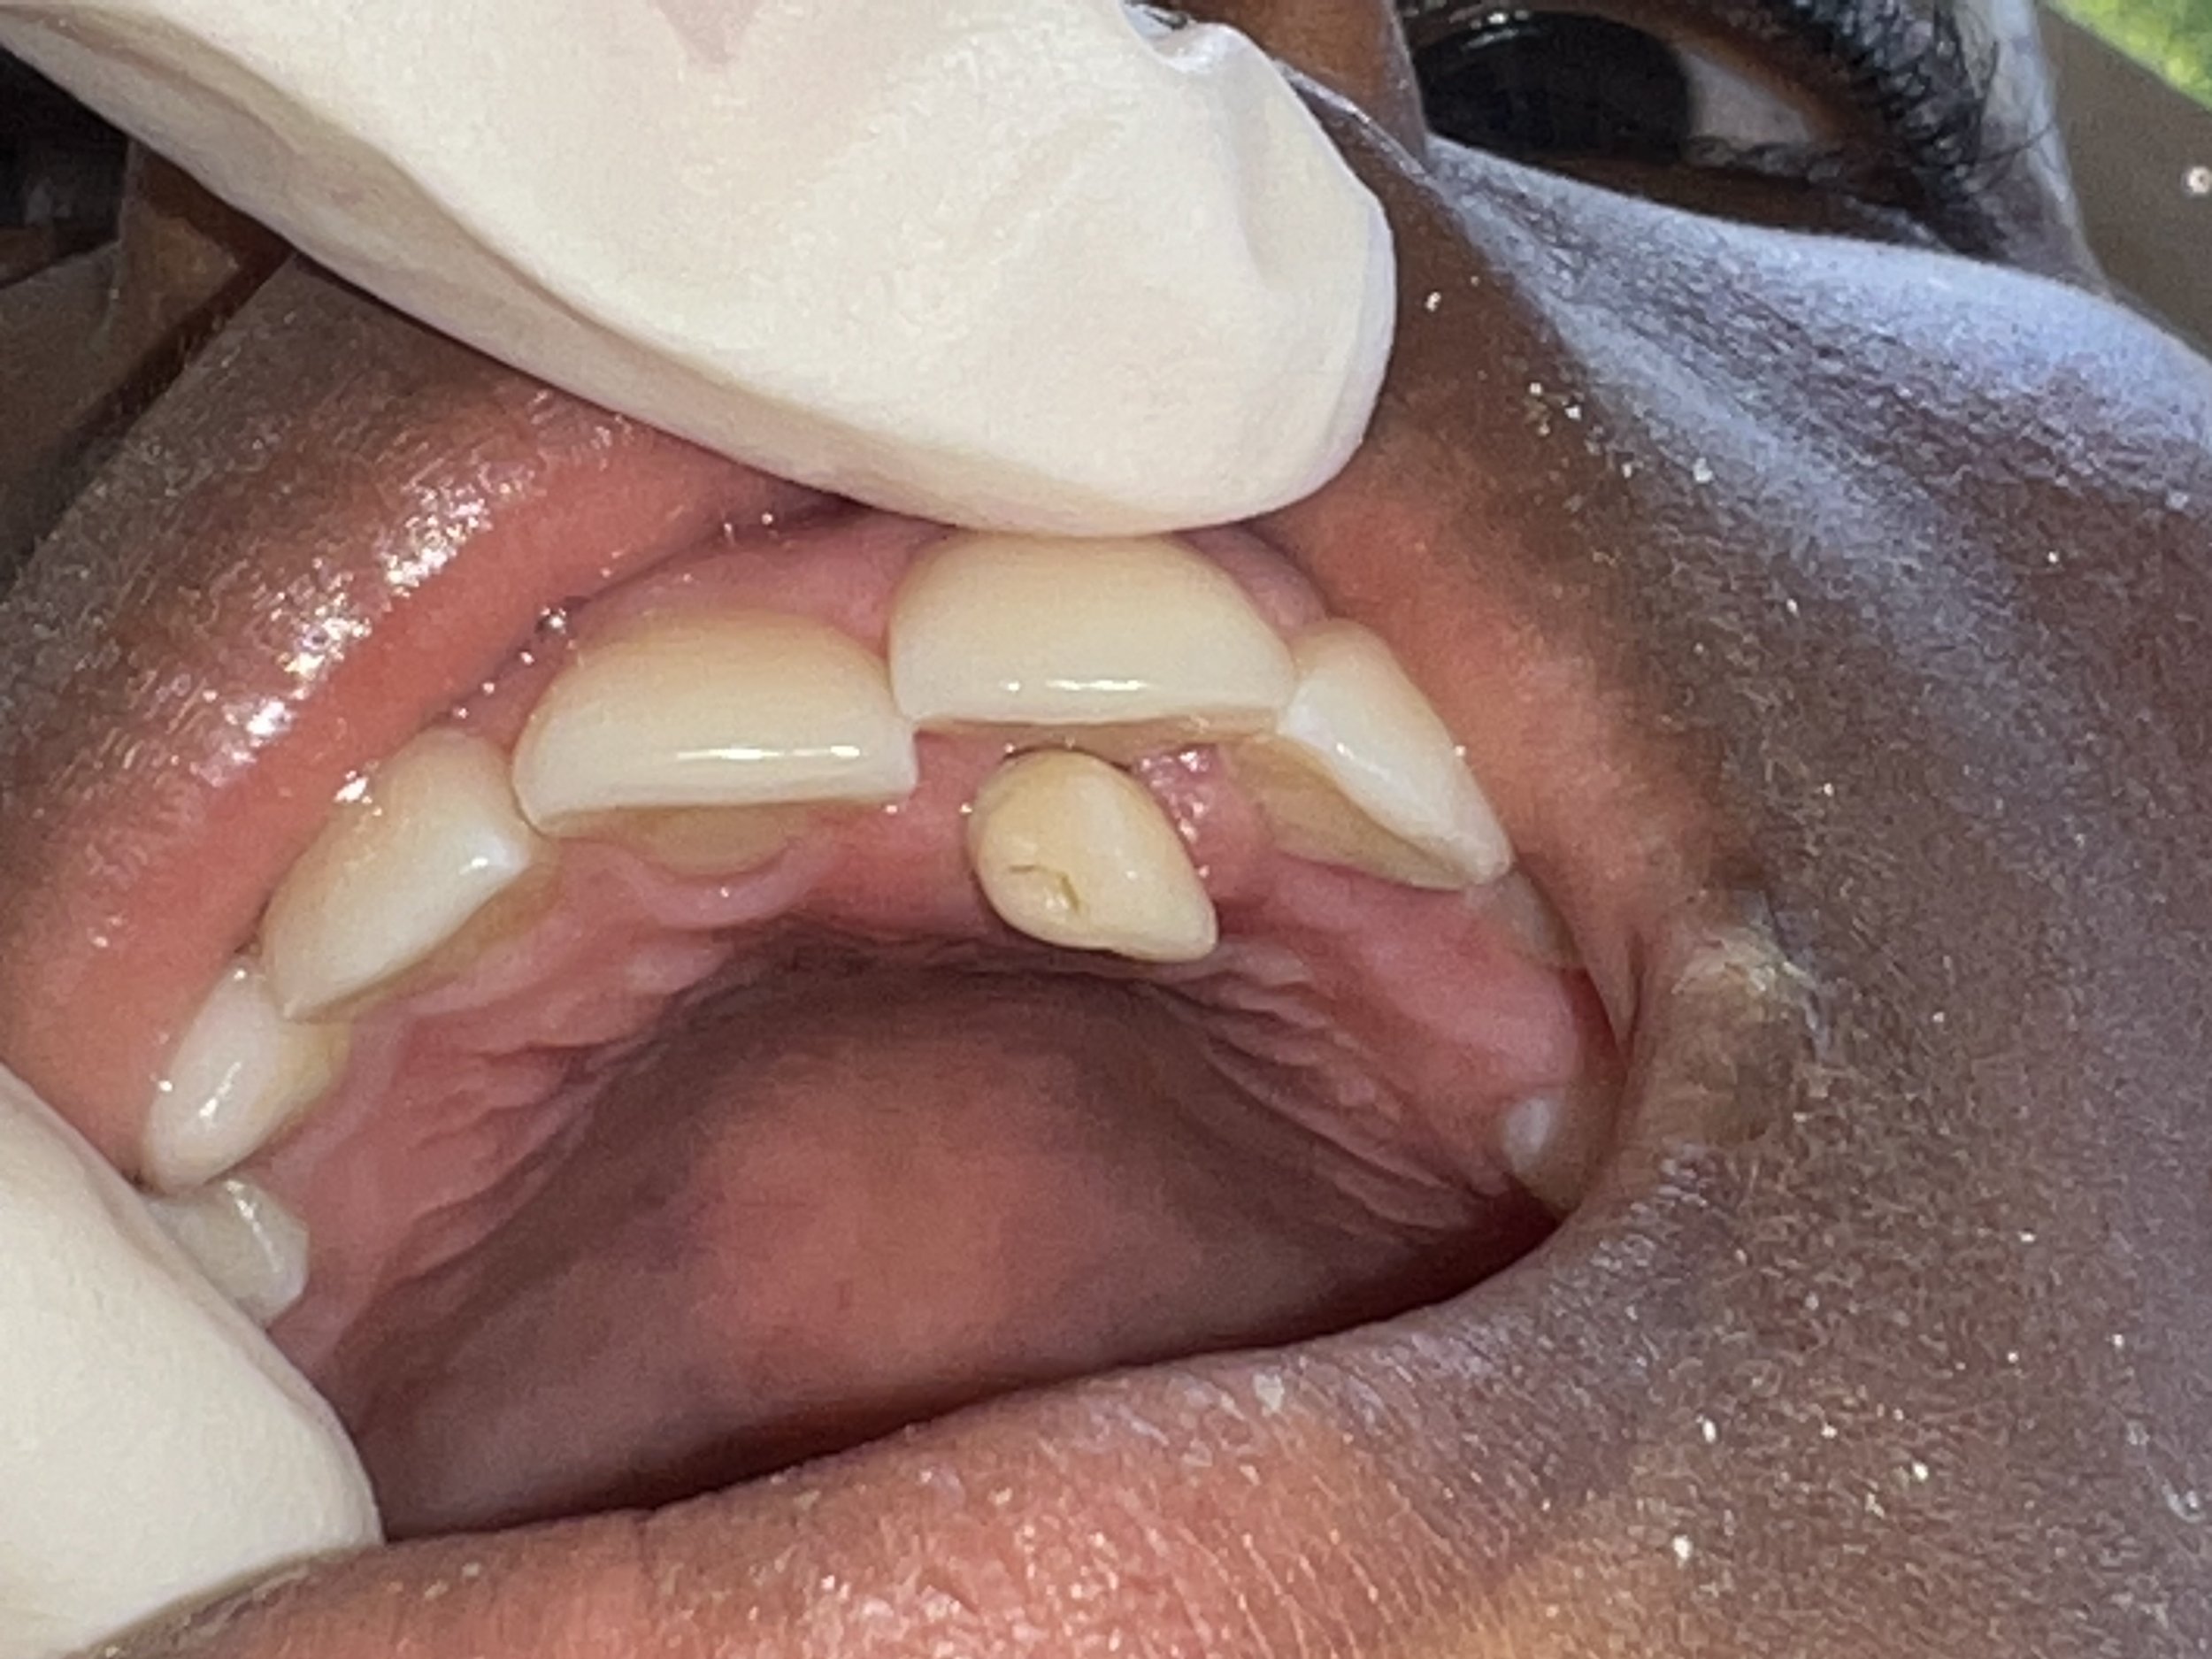

One of the most meaningful updates from this trip was seeing the success of a previously completed anterior root canal on Sandro, performed during a prior visit. His restoration is holding strong, the surrounding tissue is healthy, and his follow-up X-ray looked excellent—a beautiful reminder of the lasting impact of quality care.

The goal of this two-week trip was to properly repair an anterior root canal completed in June. A heartfelt thank you to Ultradent for generously donating the materials needed to redo this procedure. Lisa and a local dentist spent over five hours disinfecting, cleaning, and filling the canal to ensure it will last for many years. We are happy to share that the treatment was successful and that Sandro was an excellent patient throughout the process.